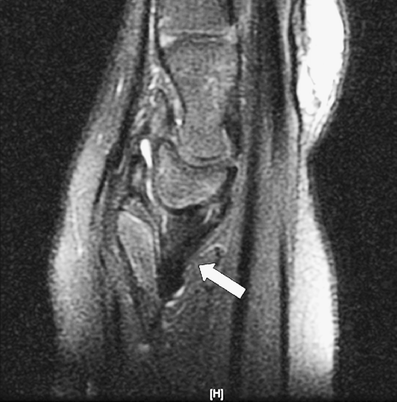

An 11-year-old girl with chronic left wrist deformity and pain underwent MRI evaluation. Coronal intermediate-weighted sequence with fat suppression showed a triangular deformity with medial tilt of the distal radius and proximal migration of the triangular-shaped lunate (Fig. 1). The triangular fibrocartilage complex (TFCC) demonstrated diffuse thickening and oblique orientation (Fig. 1, arrow). These findings are suggestive of Madelung deformity. Sagittal intermediate-weighted sequence with fat suppression showed diffuse thickening of the radiolunate ligament, suggesting Vickers ligament (Fig. 2).

Fig. 1

Coronal image